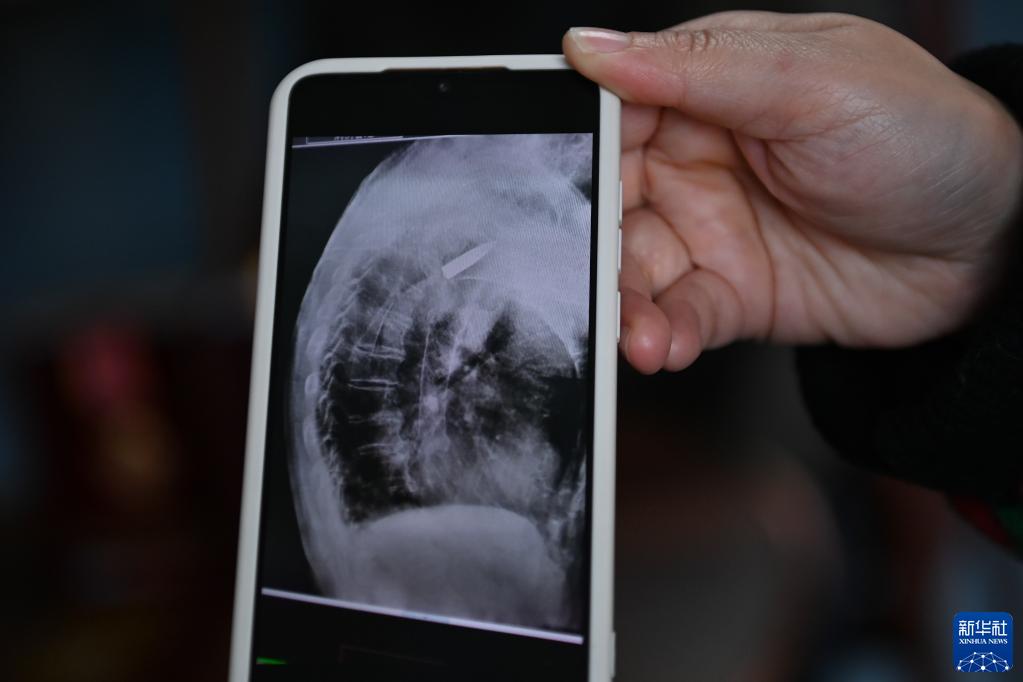

2022年11月11日上午,浙江省平湖市第一人民醫(yī)院,消化科內(nèi)鏡室主任醫(yī)師王明友正在為一位吞咽困難的96歲老人做食道支架置入手術(shù)。突然,醫(yī)生的眉頭緊皺起來:在X射線下,發(fā)現(xiàn)老人右側(cè)肩膀里居然有一顆長(zhǎng)約3.5厘米的子彈!

醫(yī)院的放射線視覺指引圖像顯示,羅錦文老人右側(cè)肩膀里有一顆長(zhǎng)約3.5厘米的子彈(3月2日攝)。新華社記者 黃宗治 攝

2022年,平湖市第一人民醫(yī)院在給老人做食道支架置入手術(shù)時(shí),X射線下清晰地看到老人肩膀里有顆長(zhǎng)約3.5厘米的子彈。而這顆子彈,早已與老人的骨頭粘在了一起,無法取出。